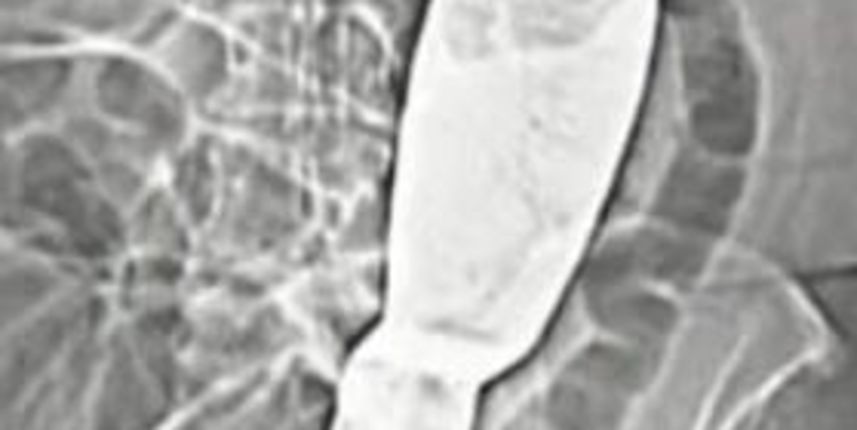

Češki kirurzi iz bolnice u gradu Ivancice suspendirani su nakon što je otkriveno da su u tijelu pacijentice nakon operacije zaboravili 30 centimetara dugačku lopaticu.

Kirurški instrument pronađen je tek pet mjeseci nakon što se nevjerojatna pogreška dogodila, a zbog užasnih bolova 66-godišnja pacijentica pomišljala je i na samoubojstvo.